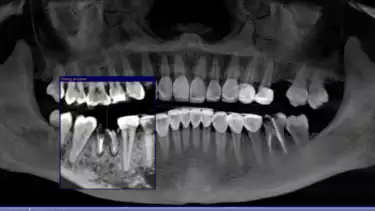

“Giginya nanti akan dicabut, tapi jangan sampai dibiarkan lama-lama. Tulang di sekitar gigi itu bisa turun, dan lama-lama gigi sebelahnya ikut goyang. Gigi atasnya juga bisa merosot turun karena tidak ada lagi penyangga di bawahnya,” jelas drg. Devya.

“Implan sangat penting untuk menjaga struktur tulang agar tidak turun dan mencegah gigi di sebelahnya bergeser,” tambah drg. Devya.